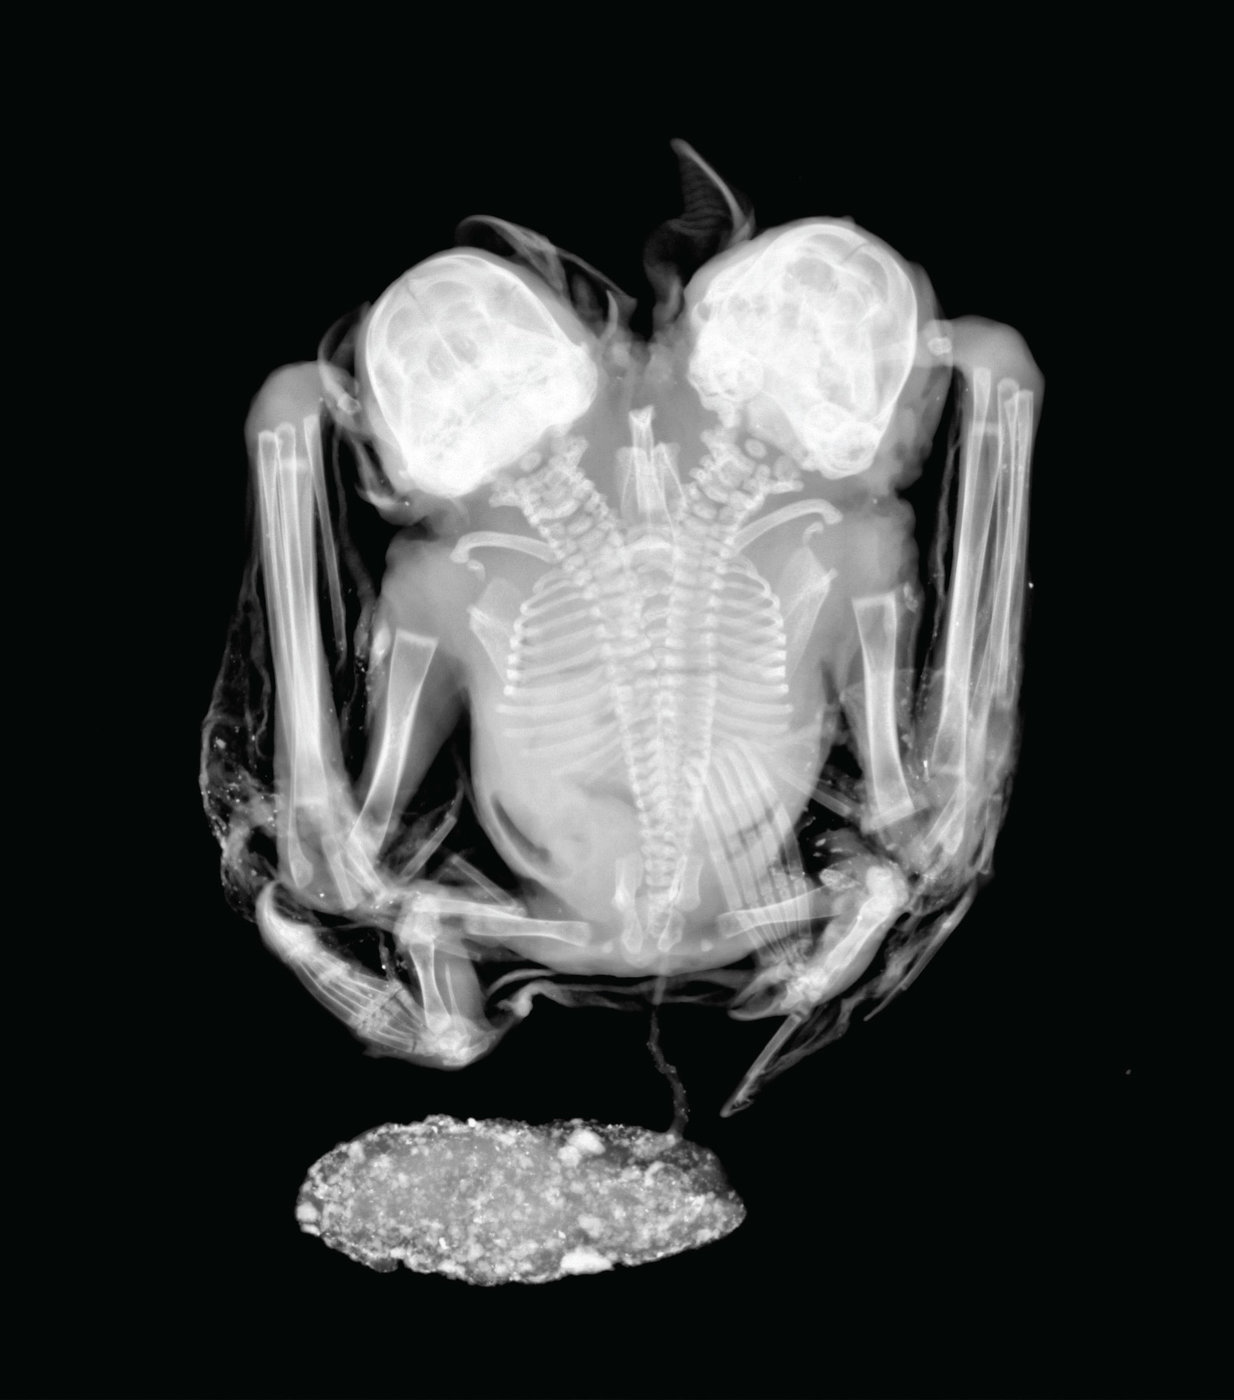

Coloanele vertebrale ale acestora au forma de „Y”, despărţindu-se la baza lombarilor, conform radiografiilor (imaginea de mai jos). De asemenea, analizele cu ultrasunete au scos la iveală că inimile celor doi lilieci au dimensiuni egale. Alte lucruri cu privire la structura internă a liliecilor nu se cunosc, întrucât cercetătorii nu doresc să folosească metode mai invazive. Fiind vorba despre un exemplar extrem de rar, oamenii de ştiinţă au hotărât să îl păstreze întreg.

Credit: Laboratório de Radiografias, Divisão de Vertebrados, Museu Nacional – UFRJ